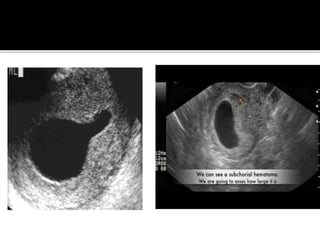

 A subchorionic haemorrhage is often seen,

prognosis.

 Features which do predict poor outcome

include:

• Fetal bradycardia : < 80 - 90 bpm

• Small or Irregular Gestational Sac : MSD -

CRL < 5 mm

• Large Subchorionic Haemorrhage